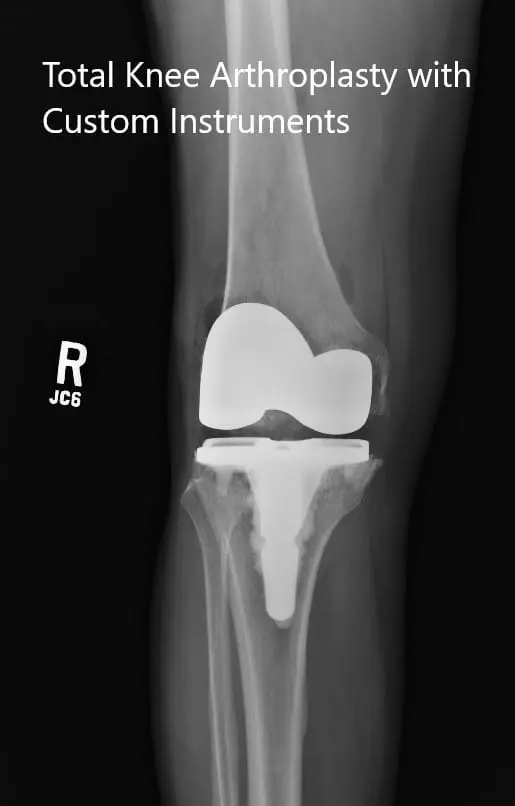

OPERATION: Right total knee replacement.

IMPLANTS USED: Femur posterior stabilized size 3 with a Persona tibia 5-degree stemmed size C with polyethylene 10-mm posterior stabilized insert with 14-mm diameter stem extension with 29-m cemented patella.

Postoperative x-rays showing the anteroposterior and lateral views of the right knee.